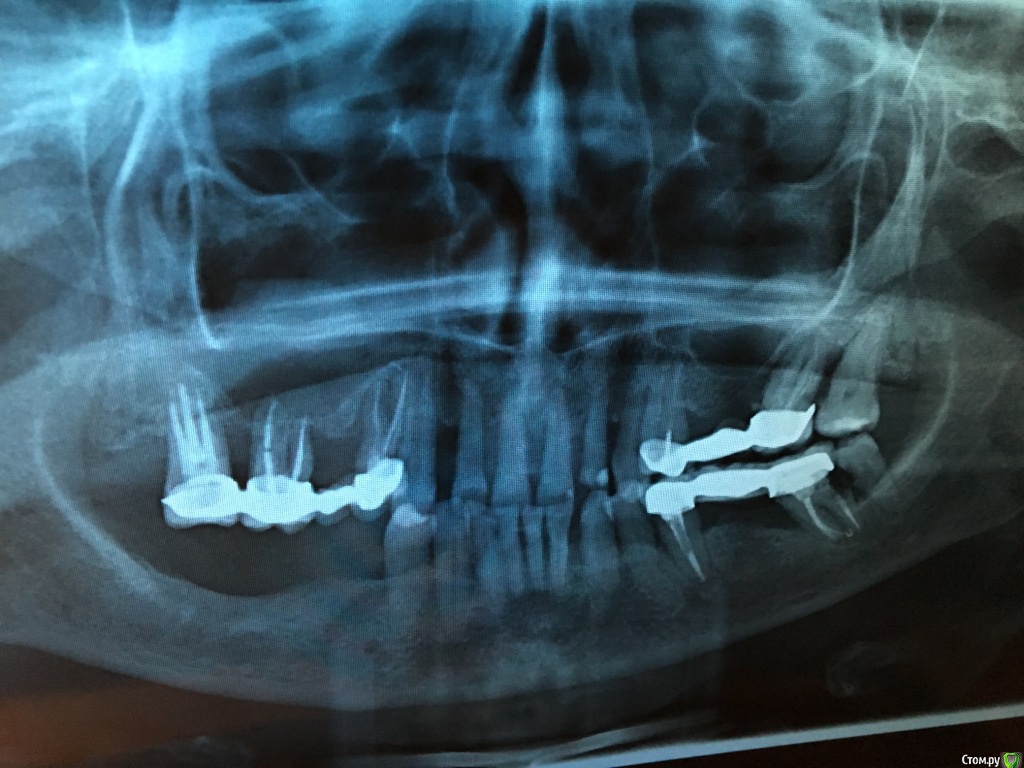

елена сок Опубликовано 29 ноября, 2019 Поделиться Опубликовано 29 ноября, 2019 Здравствуйте, уважаемые! НУЖЕН совет!!! У меня (увы!!!) жуткий пародонтит (виновата... как-то упустила...) Просто необходимо что-то с этим делать, но, к сожалению, бесконечные консультации со стамотологами в разных клиниках не привели к какому-либо решению., поскольку мнения, порой, кардинально разняться: от: 1. "оставить все как есть /пусть - и на время/,и следить и ухаживать за полостью рта крайне тщательно, 2. " все зубы под мостами удалить - и поставить импланты" , 3. " импланты противопаказаны!!!!- все зубы все-же удалить - и сделать бюгельные протезы"(вообще - жесть....) Голова кругом..... Проблема НЕ решается и я просто НЕ ЗНАЮ, что же мне делать. НЕТ вразумительного и объективного РЕАЛЬНО ВОЗМОЖНОГО в моей непростой ситуации решения. Прошу помощи! Ссылка на комментарий